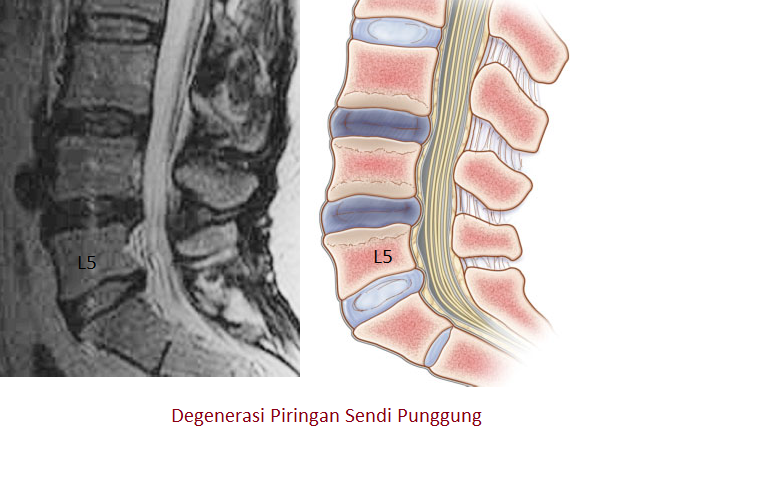

Позвонок Th10: анатомия и фото медицинских иллюстраций